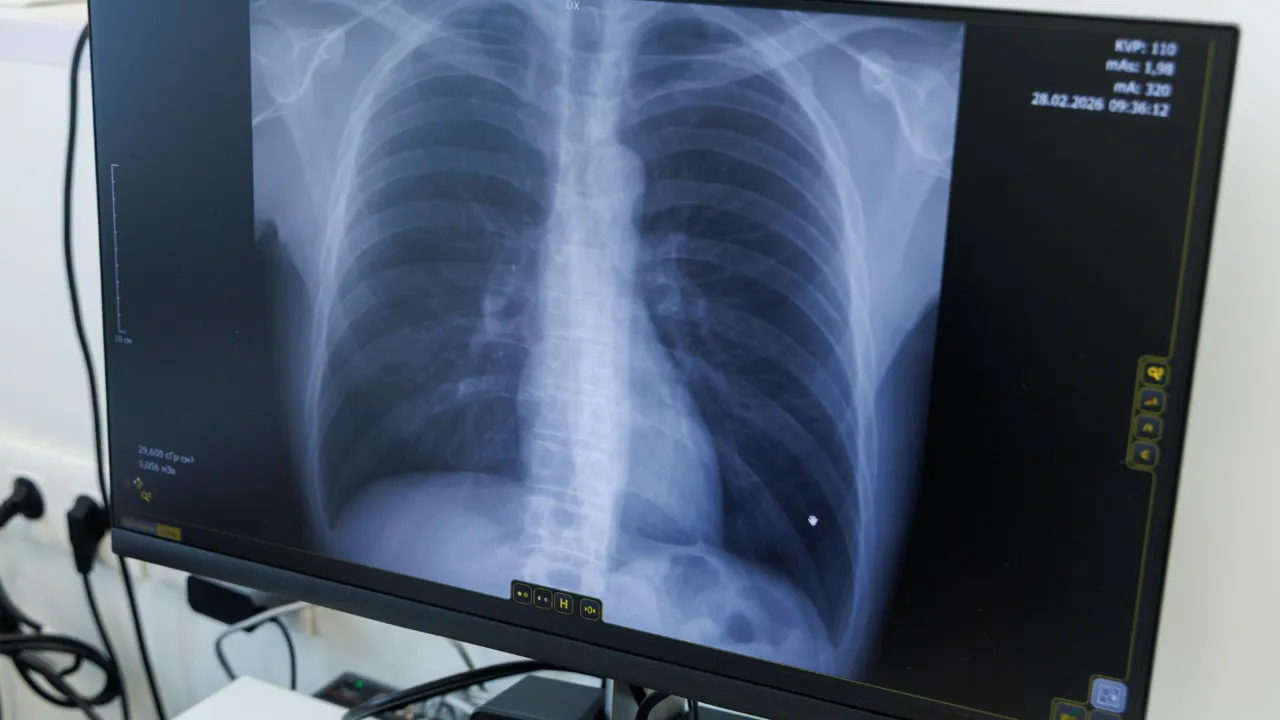

В Люберцах подвели итоги Дня открытых дверей в онкологическом центреВ Люберцах продолжают активную работу по раннему выявлению онкологических заболеваний. В Центре амбулаторной онкологической помощи Люберецкой больницы подвели итоги Дня открытых дверей, который прошел в минувшую субботу. В этот день специалисты провели базовый онкоскрининг для населения.

Обследование прошли 38 человек. Как отметила заведующая Центром Ани Баданян среди них были не только жители Люберец, но и пациенты из соседних муниципалитетов. По мнению специалиста, это свидетельствует о росте информированности людей и важности подобных проверок.

Среди прошедших скрининг было 28 женщин и 10 мужчин. По итогам осмотров и обследований у четверых пациентов были выявлены подозрения на злокачественные новообразования.

У одной женщины обнаружено новообразование молочной железы, ее направили на проведение биопсии для верификации диагноза. Еще у троих пациентов выявлены новообразования кожи. Заведующая центром сообщила, что они уже направлены на гистологический анализ, который подтвердит или исключит онкологический диагноз.

Руководитель центра подчеркнула, что Дни открытых дверей выполняют сразу две ключевые задачи. Прежде всего, напоминают людям регулярно проходить медицинские чекапы.

Во-вторых, это реальный шанс для раннего выявления болезни. Ани Баданян акцентировала внимание на том, что обнаружение онкозаболевания на ранней стадии в современной медицине практически равнозначно стопроцентному излечению. Именно отсутствие симптомов на начальных этапах делает плановые скрининги единственным способом обнаружить болезнь вовремя.

Заведующая Центром добавила, что формат «одного окна» очень востребован у населения. Пациенты могут напрямую попасть к онкологу, минуя терапевтов и узких специалистов, и получить консультацию и базовое обследование. Она привела пример реакцию одного из посетителей, который был удивлен, что такие акции проходят ежемесячно, и пообещал рассказать о возможности пройти скрининг всем соседям и родственникам.

Следующий День открытых дверей пройдет в Люберецком Центре амбулаторной онкологической помощи 29 марта.